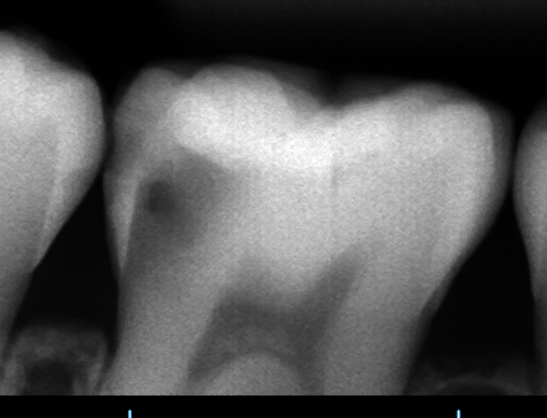

奥歯の痛みを主訴に来院されました。レントゲン検査にて神経近くまでの大きな虫歯が認められたため、MTAセメントによるVPT歯髄温存療法の選択肢とメリットデメリットを説明し、患者様はVPTを希望されました。

消毒を行い、神経に近い部分はMTAセメントを貼付します。